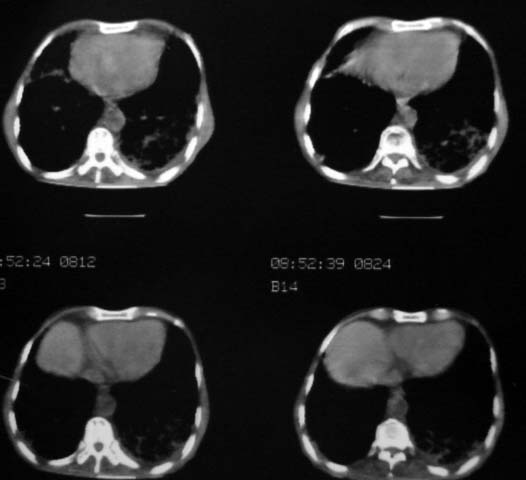

男,85岁,发热2月, 血常规:hgb99g/l.rbc2.55×1012/l.wbc3.8×109/l.n78.2%  l20.7% m1.1%.  hct26.3% .血沉20mm/hg.痰检结核杆菌阴性。ddp阳性。痰少粘稠色白。无咳血。

右上肺陈旧性肺结核灶,双肺感染灶〔大部份纤维化〕,肺气肿.

双肺继发型肺结核,肺纤维化,肺气肿,胸膜肥厚黏连。